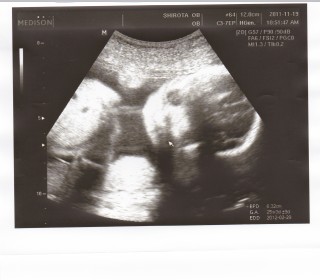

781グラムの元気な女の子です!心臓の動き、動脈の全てが正常。先生に「顔が整ってますね~可愛い」と連発されました☆嬉しいものですね。 私の体重が仕事の多忙さからか、1.1キロ減っており、この時期には珍しいとの事。糖も足りないみたいだし、しっかり頂きます。 とにかく、元気な子で良かった。正常位で胎盤も良い位置についているとの事。分娩までに、更に体力をつけるぞ!!